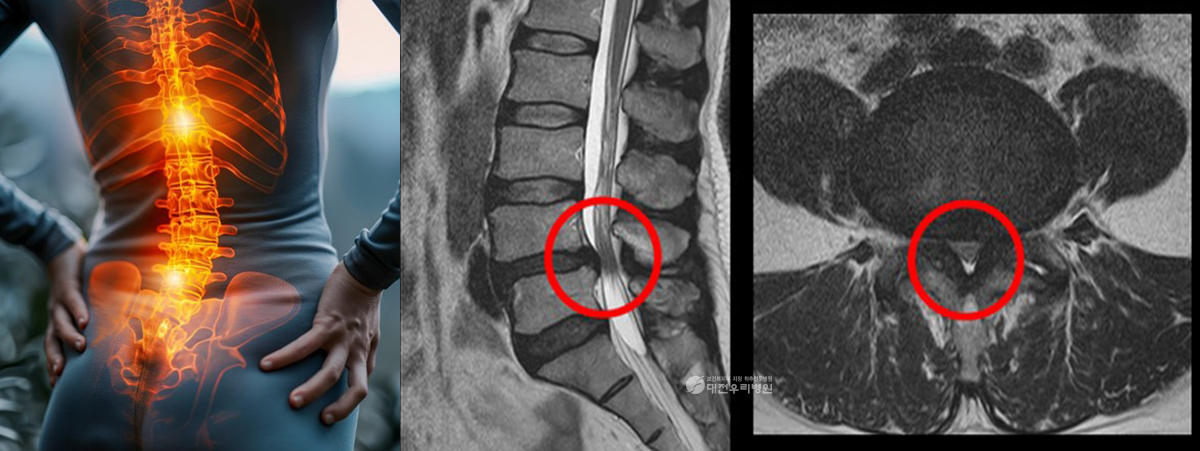

Ç㸮µð½ºÅ©´Â ôÃß »À »çÀÌÀÇ µð½ºÅ©°¡ Å»ÃâÇÏ¿© ½Å°æÀ» ¾Ð¹ÚÇÏ¸é¼ ÅëÁõÀ» À¯¹ßÇÏ´Â ÁúȯÀ¸·Î, ¾É¾Æ Àְųª Ç㸮¸¦ ¼÷ÀÏ ¶§ Áõ»óÀÌ ¾ÇȵǴ ¾ç»óÀ»

º¸ÀÌ´Â °æ¿ì°¡ ¸¹½À´Ï´Ù. ôÃß°üÇùÂøÁõÀº ³ëÈ¿Í °ü·ÃµÈ ÅðÇ༺ º¯È·Î ½Å°æÀÌ Áö³ª°¡´Â Åë·Î°¡ Á¼¾ÆÁö¸é¼ ¹ß»ýÇϸç, ¿À·¡ ¼ Àְųª °ÉÀ» ¶§ Ç㸮¿Í

´Ù¸® ÅëÁõ, Àú¸² Áõ»óÀÌ ½ÉÇØÁú ¼ö ÀÖ½À´Ï´Ù.

ÀÌ·¯ÇÑ Ã´Ãß ÁúȯÀº »ó´ç¼ö¿¡¼ ¾à¹°Ä¡·á³ª ¹°¸®Ä¡·á µî ºñ¼ö¼úÀû Ä¡·á·Î È£ÀüÀ» ±â´ëÇÒ ¼ö ÀÖÀ¸³ª, ½Å°æ ¾Ð¹ÚÀÌ ½ÉÇϰųª Áõ»óÀÌ Áö¼ÓµÇ´Â °æ¿ì¿¡´Â

¼ö¼úÀû Ä¡·á°¡ ÇÊ¿äÇÒ ¼ö ÀÖ½À´Ï´Ù. À̶§ Áß¿äÇÑ °ÍÀº ¼ö¼ú ÀÌÈÄÀÇ È¸º¹ °úÁ¤ÀÔ´Ï´Ù.